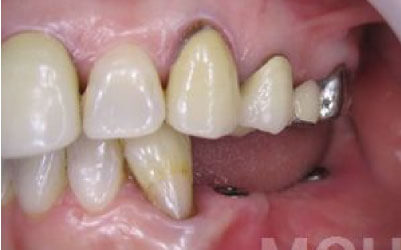

お口の状態や噛み合わせによって異なるため、一概には言えませんが、基本的には奥歯、特に一番奥とその手前の大臼歯部分がおすすめです。

噛み合わせの力の約60%以上がこの奥の二本の歯で支えられているため、ここをインプラントでしっかり治療することが非常に効果的です。

3 歯周病でインプラントが抜けるリスク

細菌(歯垢)の影響で、インプラントを支える歯ぐきや骨が痩せてしまうことがあります。

そのため、インプラント治療だけでなく、残っている天然歯の歯周病検査や治療もしっかり行うことが非常に重要です。

今回のご質問ですが、抜けた部分の骨が薄いなどの理由で「インプラントはできない」と言われた可能性があります。

前歯はもともと骨が薄く、歯が抜けると時間の経過とともにさらに骨が痩せてきてしまうので、インプラント治療の難易度が高い場所です。

ただ結論からお話すると、インプラント治療は可能です。

なぜなら、もし仮に骨が薄くても、骨の治療によって厚みが増せば、安全にインプラント治療が行えるからです。

なお、前歯のインプラント治療をご希望の方には、注意していただきたい点が4つほどあります。

1)インプラント治療を行う前に、骨の治療が必要かもしれません。